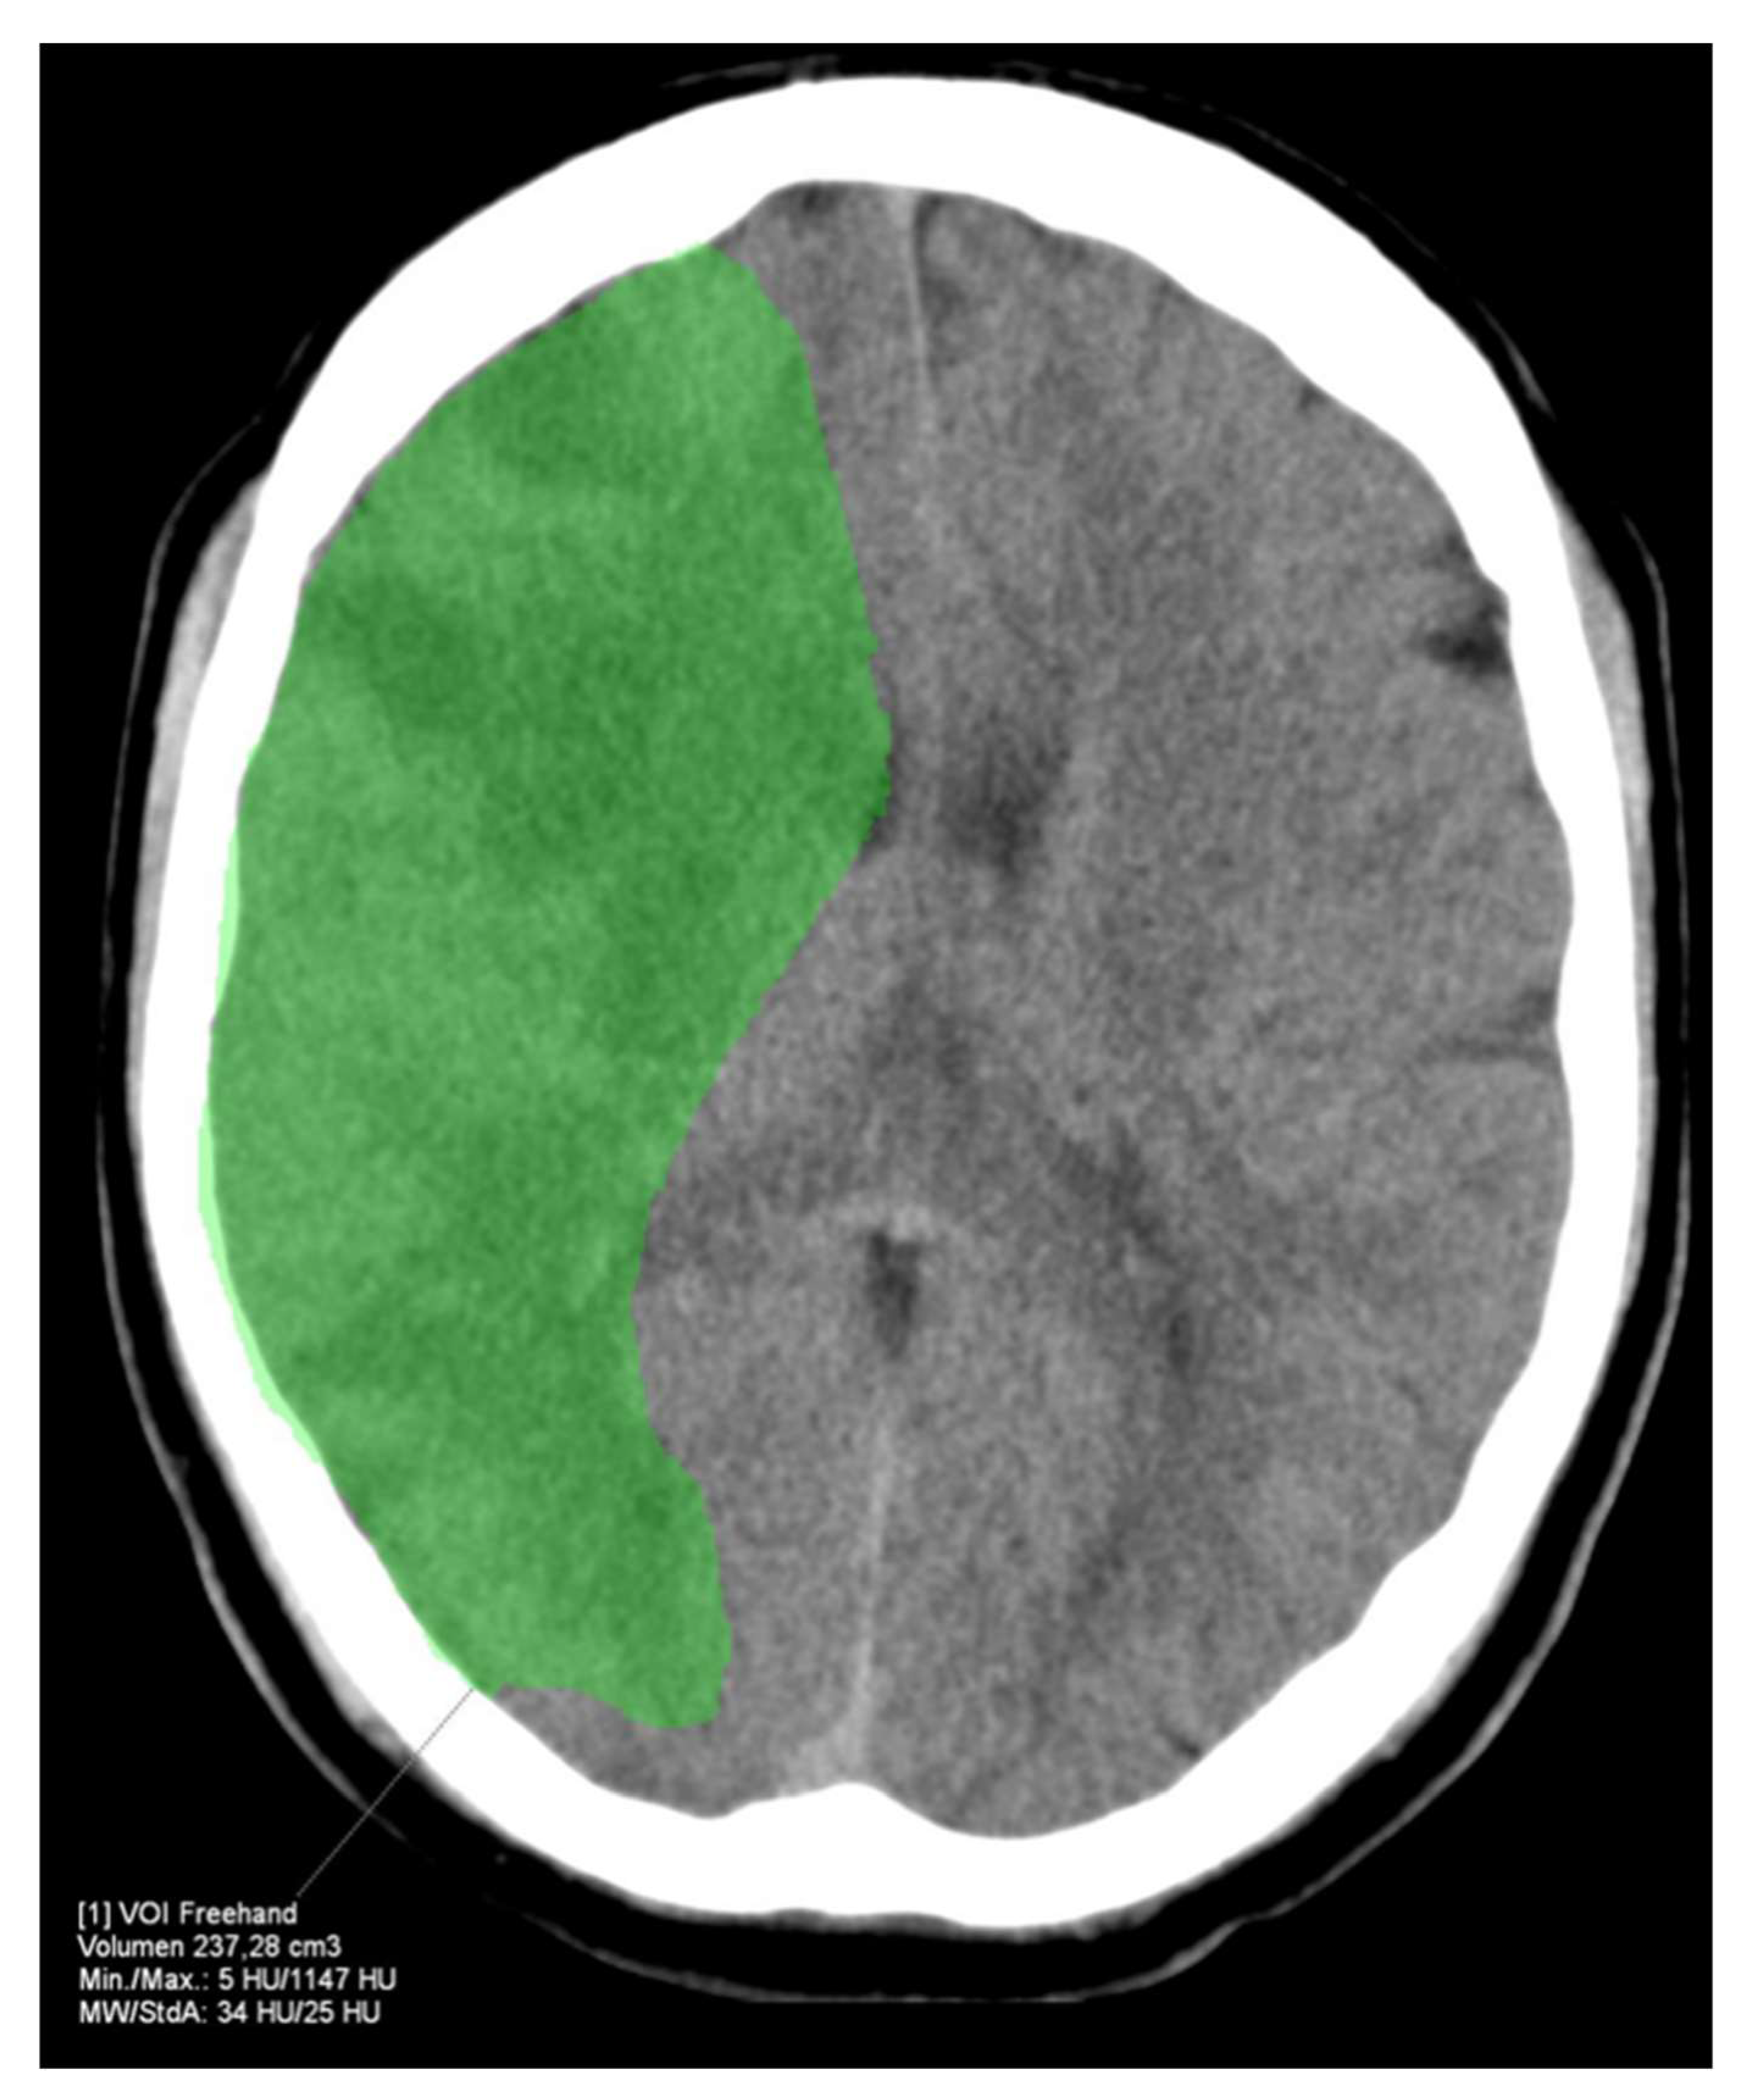

The HVs differed significantly between RAPID and Syngo (−21.7 ± 37.9 mL, p < 0.001) as well as Brainomix and Syngo (−28.9 ± 45.1 mL, p < 0.001), while there were no significant differences between RAPID and Brainomix (−8.3 ± 41.0 mL, p = 0.22). The same could be observed for the mismatch volumes, which did not show significant differences between RAPID and Brainomix (3.8 ± 43.5 mL, p = 0.29), but between Brainomix and Syngo (−27.7 ± 46.3 mL, p < 0.001) as well as RAPID and Syngo (−25.3 ± 41.4 mL, p < 0.001). However, correlation of the mismatch volumes was high among all software packages (r > 0.8, p < 0.001). All software packages showed small differences (between 0.9 and 3.1 mL) in the indicated ischemic core volumes (ICV) without significant differences (p > 0.3). Median HIR was 0.6 (0.4–0.7) for all software applications. Figure 3 shows the automatically generated perfusion results by packages A, B, and C of a patient with M1-occlusion of the right hemisphere. The FIV on follow-up CT 24 h after futile recanalization is shown on Figure 4.

Figure 4. FIV of the example patient from Figure 3 24 h after futile recanalization. The FIV corresponds well with the HV indicated by RAPID.